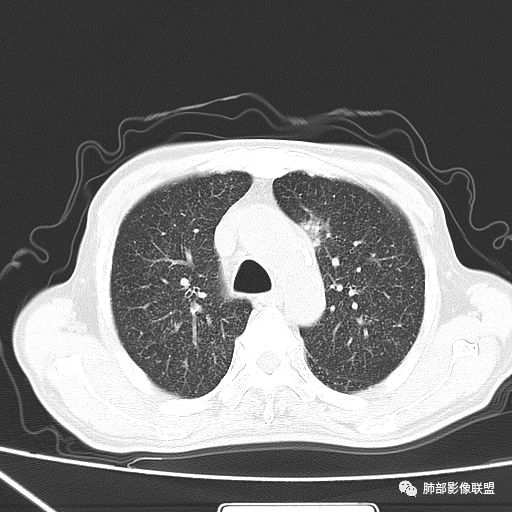

2019-10-20复查CT如下:

两肺弥漫性粟粒样结节伴左上肺小结节,呈三均匀分布,有结核的临床表现,支持血性播散性肺结核。

大小、分布均匀,边缘清楚

细小结节,弥漫,撒米粒样——血道来源

血道来源的病灶,均匀、细微,而且部分有分支状,都符合粟粒型肺结核

急性血行播散型肺结核  两肺广泛分布粟粒大小的结节状密度增高影,具有大小均匀、分布均匀、密度均匀的典型“三均匀”特征,注意急性血播病灶非常小,一般粟粒影直径1~2mm。

病灶密集者出现肺外围血管影不清或减少。